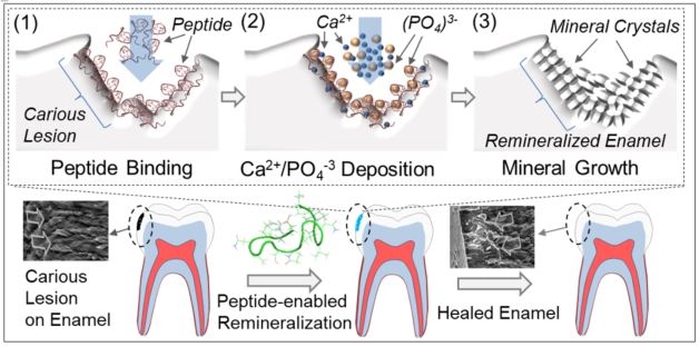

في عام 2018 ، أعلن باحثون في جامعة واشنطن عن تطوير علاج يعتمد على الببتيدات – سلاسل قصيرة من الأحماض الأمينية ، مرتبطة بروابط ببتيدية ، وهي ليست طويلة بما يكفي لاعتبارها بروتينات كاملة.

عند تطبيقه على آفات الأسنان المصطنعة في بيئة معملية ، أعاد المنتج تمعدن مينا الأسنان ، و “يشفي” الآفة بشكل فعال.

لتطوير علاجهم الجديد ، لجأ الفريق إلى أحد البروتينات التي تنتجها خلايا المينوبلاست. تلعب هذه البروتينات ، المسماة بالأميلوجينين ، دورًا رئيسيًا في تنظيم تكوين مينا الأسنان.

صمم الفريق الببتيدات بناءً على هذا البروتين وابتكر علاجًا باستخدام الببتيد كعنصر نشط.

قاموا بتطبيقه على آفات الأسنان في بيئة معملية ووجدوا أنه ساعد في تكوين طبقة معدنية جديدة في المناطق المنزوعة المعادن ، ودمجها مع المينا تحتها.

لقد عالجوا أيضًا الآفات المماثلة بالفلورايد ، لكن العلاج الببتيد فقط أدى إلى إعادة تمعدن طبقة سميكة نسبيًا – تشبه بنية المينا الصحية.